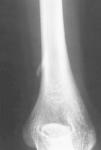

En el estudio radiológico se apreció una prominencia ósea situada en la cara anteromedial del húmero, a unos 5 cm por encima de la epitróclea, cuyo tamaño era de unos 2 cm de largo, de base ancha y forma alargada dirigida en dirección inferior y anterior (Fig. 1). Ante el diagnóstico de apófisis supraepitroclear, y debido a la clínica neurovascular que presentaba la paciente, se optó por el tratamiento quirúrgico.

ABFigura 1. A: Rx AP. Se aprecia la apófisis supraepitroclear en dirección craneocaudal y hacia medial. B: Rx lateral.